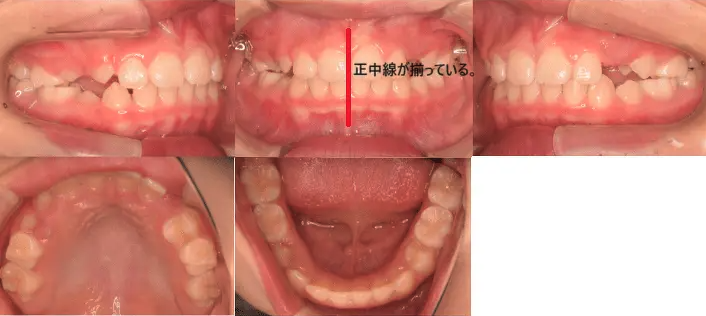

治療例③25歳7ヶ月

主訴 前歯がガタガタ。正中線もずれている。

治療内容 小臼歯4本を抜歯した後、インビザラインを使用して主訴である叢生の改善を行った。

治療期間 2年

費用 80万円

【治療前】

【治療後】